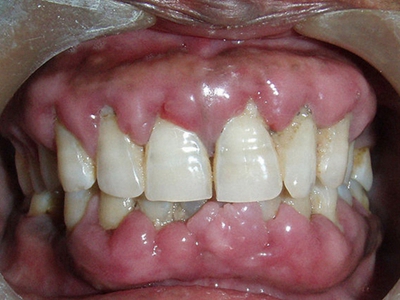

牙龈炎是发生于牙龈组织的炎症,患者可出现牙龈出血伴肿胀、发红、正常形态改变和偶尔不适等症状。本病主要由口腔卫生状况差导致,包括口腔不洁、牙菌斑等,诊断依据临床检查,治疗包括专业牙齿清洁和加强家庭口腔卫生。

牙龈炎可先引起牙齿与牙龈之间的沟(龈沟)加深,然后牙龈充血,炎症围绕一个或多个牙齿,伴牙龈乳头肿胀和易出血。一般无痛,可自行消退,也可维持轻度炎症数年。